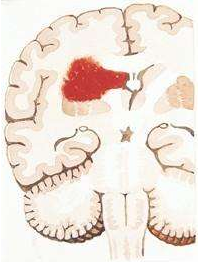

相关图片